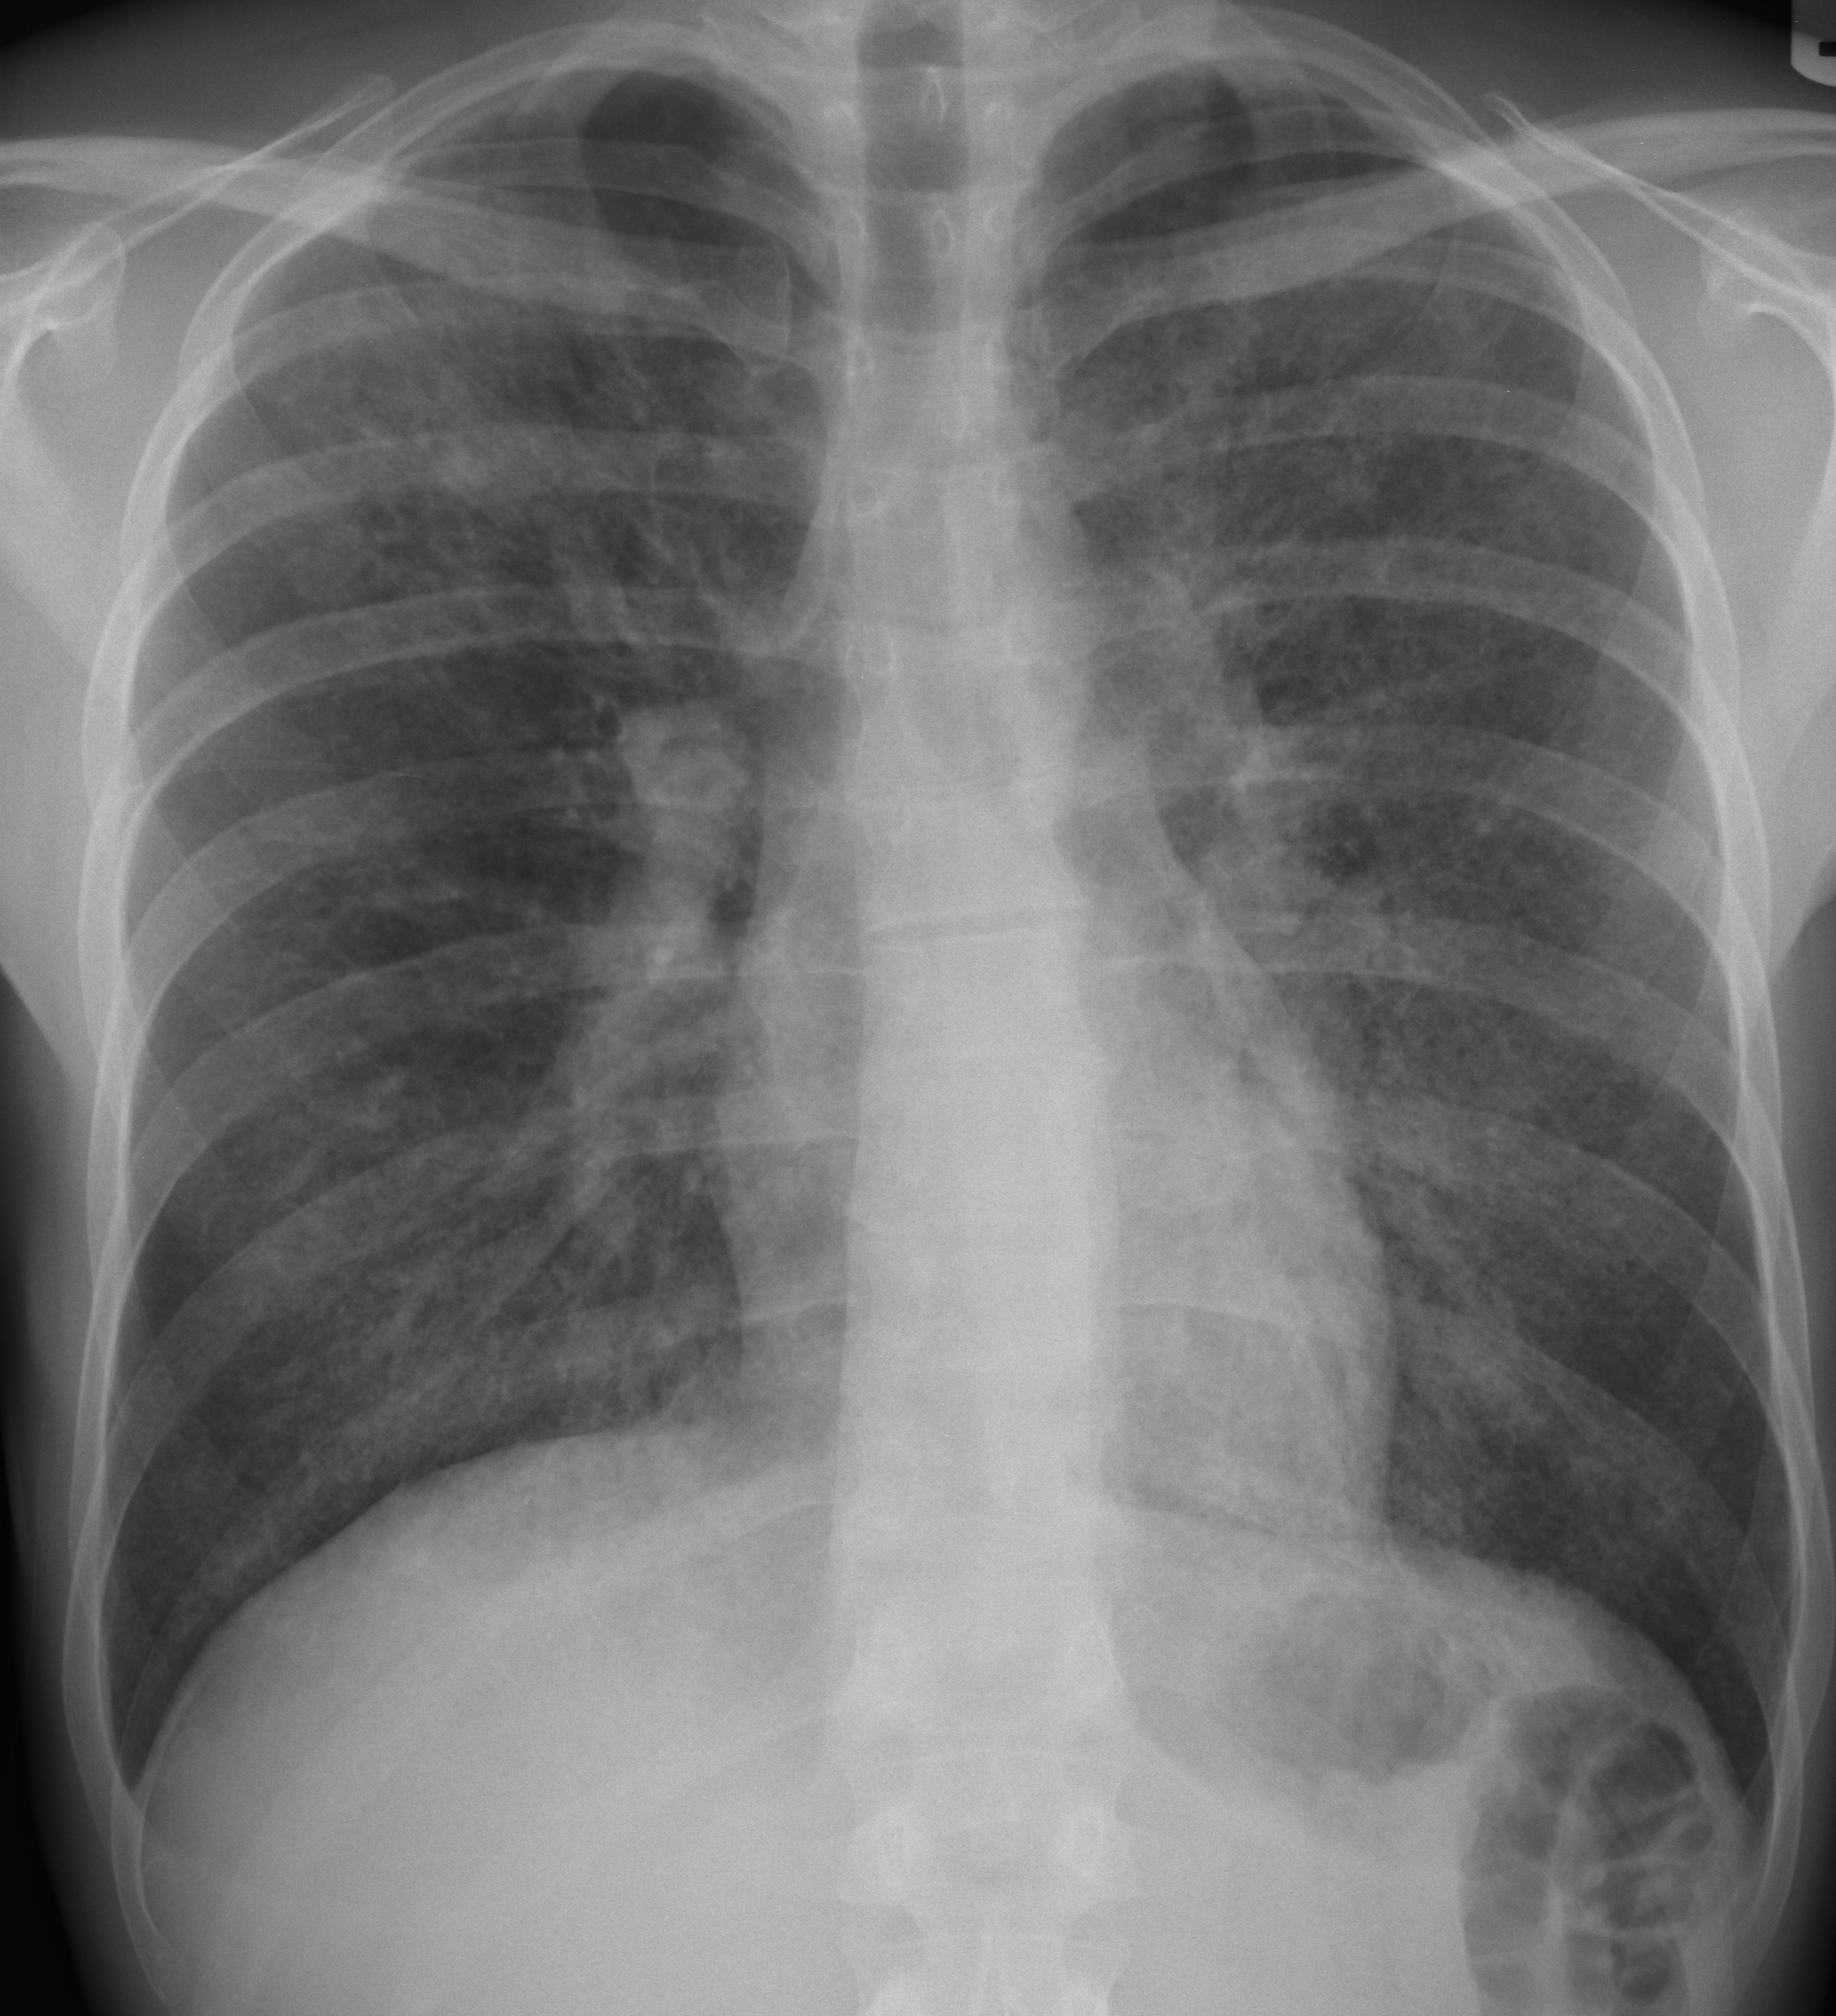

흉부 엑스레이는 ILD에 대해 63%의 민감도와 93%의 특이도를 보인다.[6] 컴퓨터 단층 촬영의 발전으로 인해 흉부 CT 스캔은 ILD의 선호되는 진단 검사로 폐 생검을 대체했다. 흉부 CT 스캔은 ILD에 대해 91%의 민감도와 71%의 특이도를 보인다.[6] 고소득 국가에서는 ILD 환자의 10% 미만이 진단 평가의 일환으로 폐 생검을 받는다.[14]

흉부 방사선 사진은 일반적으로 간질성 폐 질환을 감지하기 위한 첫 번째 검사이지만, 특히 질병 과정의 초기에는 흉부 방사선 사진이 최대 10%의 환자에서 정상으로 나타날 수 있다.[17][18]

진단상 중요한 것은 영상 검사이다. 단순 X선 촬영 및 흉부 CT에서는 '''유리 갈림 음영'''이 특징적이다. 이는 비교적 균일하게 농도가 올라간, 흐릿한 폐 음영이다. 진행되면 섬유화를 반영하여 벌집 모양을 띠게 된다.